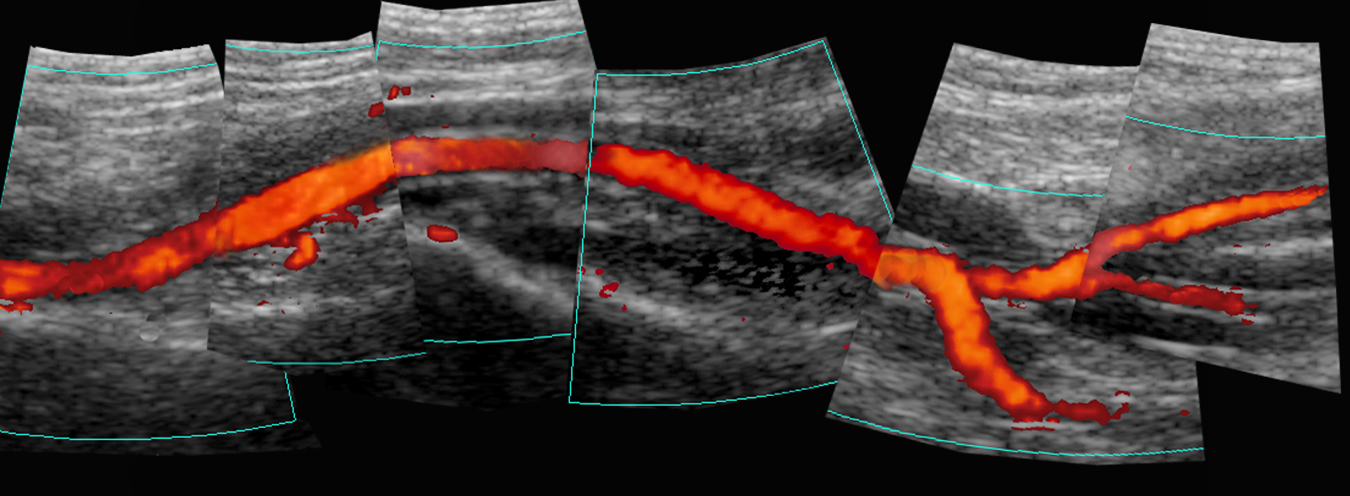

popliteal artery power doppler composite US (proximal to PTA)

tibio-peroneal trunk US with colour

proximal PTA spectral US